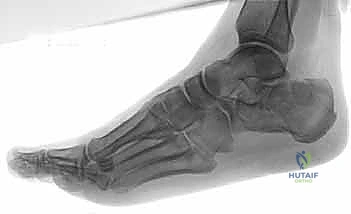

- التصوير بالأشعة السينية (X-rays): لأخذ فكرة أولية عن الكسر (زوايا بوهلر وجيسان - Bohler’s and Gissane’s angles).

- الأشعة المقطعية (CT Scan): وهي الخطوة الأهم والأكثر حيوية. توفر الأشعة المقطعية صوراً ثلاثية الأبعاد وتقاطعاً دقيقاً للكسر، مما يسمح بتصنيف الكسر (نظام ساندرز - Sanders Classification) وتحديد عدد الشظايا العظمية ومدى انزياحها داخل المفصل. بناءً على هذه الأشعة، يضع الدكتور هطيف خطته الجراحية الدقيقة.

5. التثبيت النهائي باستخدام الشرائح والمسامير (Plating)

يتم وضع شريحة تيتانيوم (Titanium Plate) مصممة خصيصاً لتطابق الشكل التشريحي لعظم الكعب. يتم تثبيت هذه الشريحة بمسامير قوية لتوفير ثبات ميكانيكي صلب يسمح بالالتئام السليم ويمنع انهيار العظم مرة أخرى. في بعض الحالات التي يوجد فيها فراغ عظمي كبير، قد يستخدم الدكتور هطيف طعوماً عظمية (Bone Grafts) لملء الفراغ.